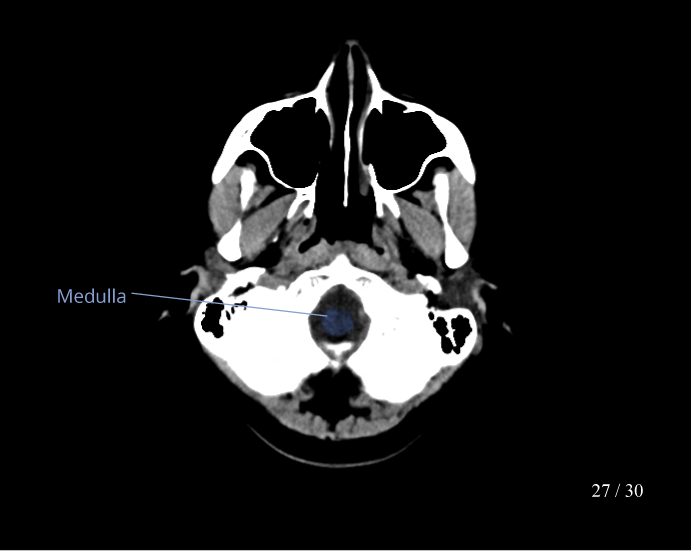

CT Brain Anatomy